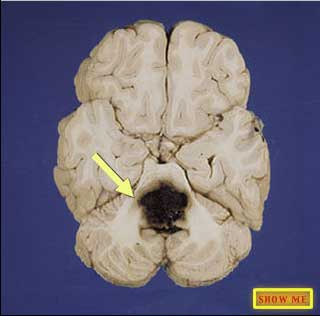

Can you find the hemorrhage?

click to view answer